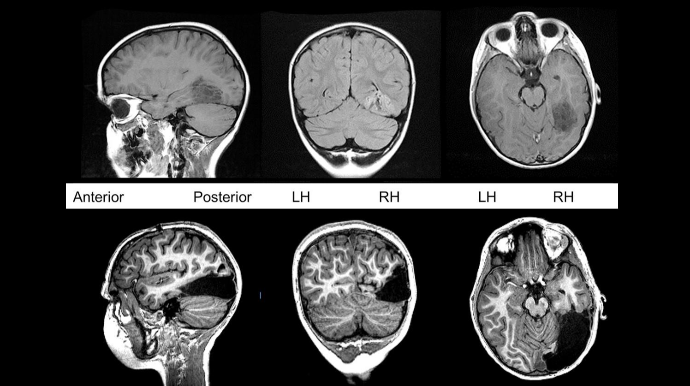

London Universiteti Kollecinin (UCL) tədqiqatçıları COVID-19 üzündən beyin xəstəliklərinin artacağı qənaətinə gəliblər.

Məsələyə dair elmi məqalədə koronavirus xəstəliyinin 16-85 yaş arasındakı 43 nəfərdə necə keçdiyi araşdırılıb.

Araşdırma nəticəsində həmin xəstələrin 10 nəfərində beyinin fəaliyyəti müvəqqəti pozulub, 12 nəfərində beyin iltihabı yaranıb. Bununla yanaşı, insult və s. ciddi fəsadlar da özünü göstərib. (“Report”)